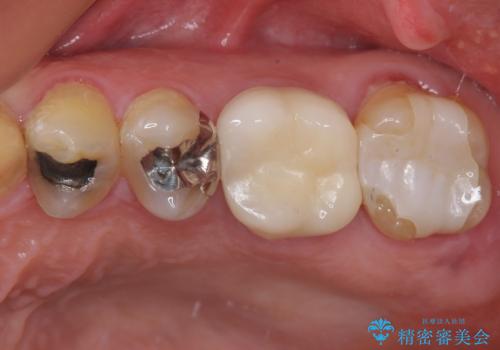

- ブリッジの歯のないところにインプラントを入れて、銀歯を白くやり替えたいと来院された患者様です。

歯の欠損している箇所にはインプラント治療をし、銀歯と仮詰めの部分はセラミックインレーにて補綴することとしました。

すべての治療の前に親知らずの抜歯も行っています。